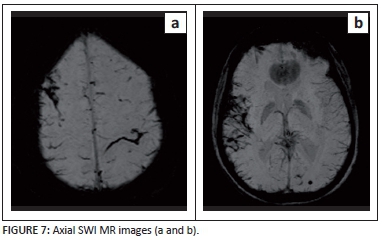

A 40-year-old lady had a CT and an MRI scan of her brain for investigation of severe headache following recent recurrent bowel surgery. The post-operative course was complicated by abdominal wall haematoma, and she required multiple blood transfusions. The background history of multiple previous bowel resections and chronic anti-inflammatory therapy for inflammatory bowel disease was noted.

Describe the relevant imaging findings and formulate the most appropriate clinical diagnosis.